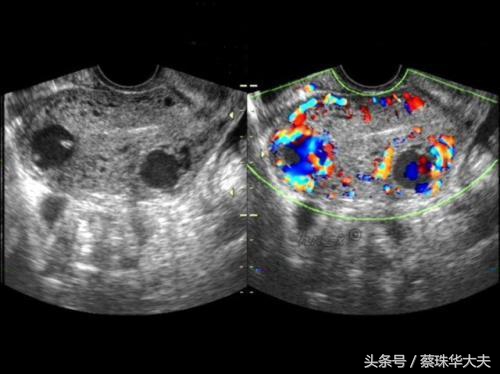

黄体囊肿特点里面回声有点杂,B超会经常描述成混合性回声。如果当月排出来的卵没有怀孕,那黄体囊肿就没有任务了,就自行萎缩掉。

这些囊肿的特点是月经干净后复查,囊肿不会缩小,大小不变或会增大。或者B超下看上去回声乱糟糟。这些囊肿需要及时的治疗。